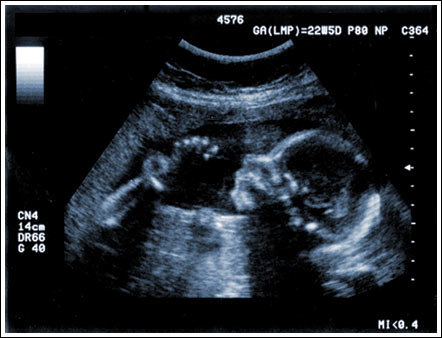

By transmitting acoustic energy into the body and receiving and processing the returning reflections, phased-array ultrasound systems can generate images of internal organs and structures, map blood flow and tissue motion, and provide highly accurate blood velocity information. Historically, the large number of high-performance phased-array transmitters and receivers required to implement these imaging systems resulted in large and expensive cart-based implementations. Recently, advances in integration have allowed system designers to migrate to smaller, lower cost, and more portable imaging solutions with performance approaching these larger systems. The challenge moving forward is to continue to drive the integration of these solutions, while increasing their performance and diagnostic capabilities.